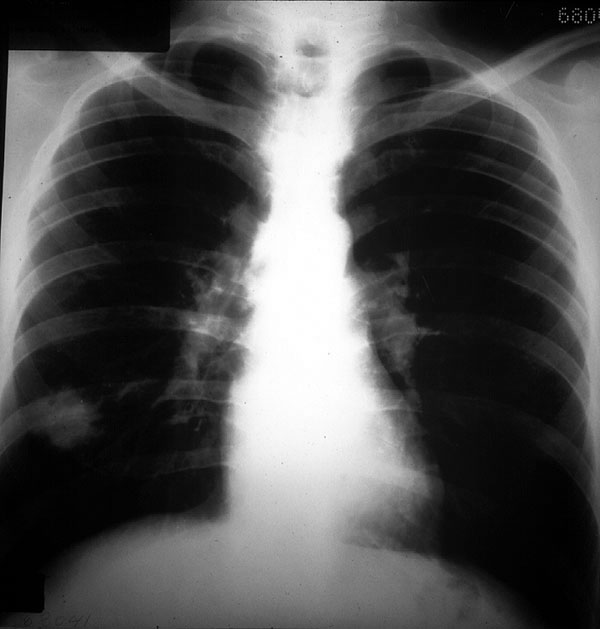

Placa 22